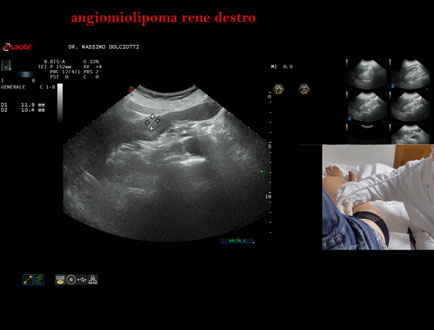

Età Paziente: F 78 anni

Motivazione dell'esame: riscontro occasionale.

Commento all'esame: le immagini ed il video documentano in sede mesorenale corticale del rene destro, immagine iperecogena, ovalare, delle dimensioni di 11,9 x 10,4 mm, da ricondurre ad angiomiolipoma.

Conclusioni: angiomiolipoma del rene destro (angiomyolipoma of the right kidney).